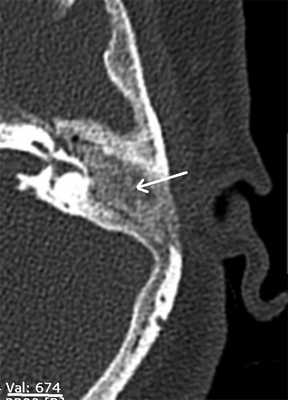

Анализ данных МСКТ показал, что реимплантрованная костная ткань имеет меньшую плотность, чем наружный кортикальный слой сосцевидного отростка, и варьировала от 350 до 680 едН. В подавляющем большинстве исследований по данным МСКТ не визуализировалась четкая граница между пересаженной костной стружкой и окружающей костной тканью (рис. 3). Лишь в 6 (18%) случаях можно было наблюдать тонкую прослойку низкой плотности между реимплантированной и окружающей костной тканью. По плотности данная прослойка сопоставима с соединительной тканью. Данные МСКТ также позволили в 2 случаях (8%) предположить рецидив холестеатомы. Этим пациентам была выполнена санирующая реоперация по открытому типу (с формированием МП). Интраоперационные находки подтвердили данные МСКТ височных костей и необходимость реоперации.

Рис. 3. МСКТ левой височной кости, аксиальная проекция. Стрелка — имплантированная костная стружка.